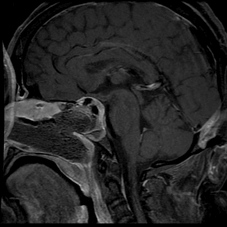

Case 2: 35/ M

- Pre-operative sagittal contrast enhanced T1W image shows a sellar mass with suprasellar extension (Figure 4)

- Intra-operative MRI (Figure 5) shows residual enhancing tumour, which was then taken up again for resection. Post operative MRI (Figure 6) shows a thin enhancing capsule with no residual tumour.

Figure 4